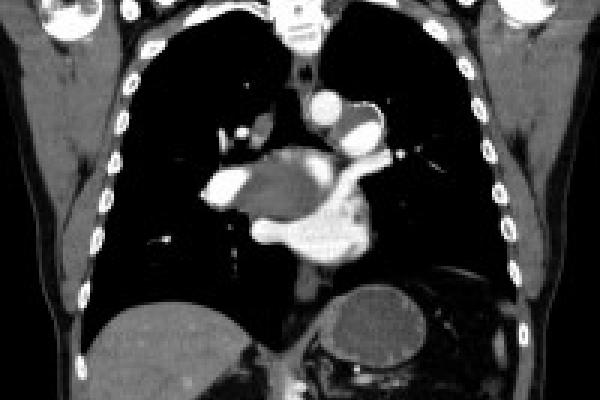

Temple patient's PTE CT scan

• His own pulmonologist performed some preliminary scans and suspected that Kevin may have CTEPH, or chronic thromboembolic pulmonary hypertension – a rare and often fatal form of pulmonary hypertension. It is an unusual condition that many hospitals haven’t seen or treated.

• Over a number of months, my team and I conducted extensive testing and were able to conclusively diagnose Kevin with CTEPH.

• After reviewing Kevin’s test results, I told him the size of his clots meant that he was going to need complex surgery called PTE (pulmonary thromboendarterectomy), which is performed at only a few hospitals in the US.